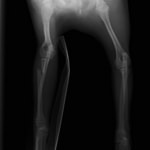

ペルシャ猫 11ヶ月齢 雄

他院にて左大腿骨遠位の成長板骨折(salter-harrisⅠ型)が認められており、治療相談を目的として来院。当院にて、キルシュナーワイヤーを用いたピンニングにより骨折部位の整復を行いました。術後の経過は良好で、現在も経過観察中です。

術前レントゲン